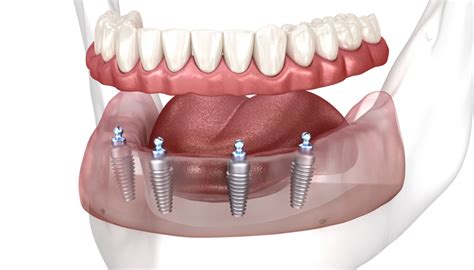

1. Prótesis Completa Fija Mandibular sobre Implantes

Si se escoge esta opción, el paciente necesita un mínimo de 5 a 6 implantes colocados en la zona anterior de la mandíbula, para construir una prótesis de 10 dientes. Por la pérdida de hueso importante que suelen tener los pacientes, la prótesis suele reemplazar tanto los dientes como la encía perdida.

Esta prótesis es fija para el paciente (el paciente no puede quitarse la prótesis), pero puede ser extraída por el dentista (si está atornillada), en caso de que sea necesario retocarla. Esta opción tiene más estabilidad y retención que una dentadura completa convencional o una sobredentadura sobre implantes. Se ha demostrado que esta restauración estabiliza la altura ósea a lo largo del tiempo, deteniendo el proceso de atrofia ósea y los efectos estéticos de envejecimiento de la cara asociados a esta.

Como otras prótesis, la dentadura fija completa puede romperse, y los tornillos pueden fracturarse o aflojarse. El paciente puede tener a veces dificultades con el mantenimiento de la higiene diaria alrededor de la dentadura. En general, esta prótesis fija es más difícil de limpiar que la sobredentadura.